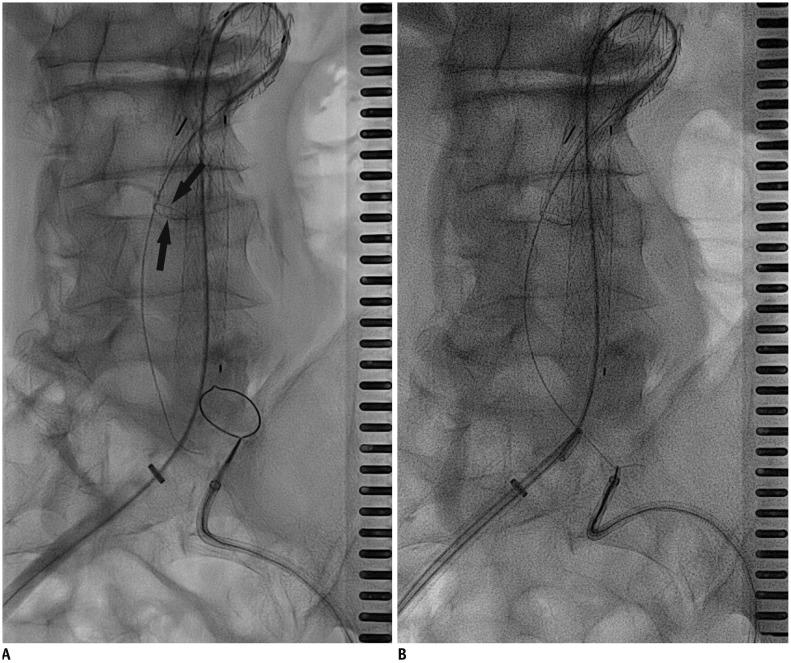

Abdominal aortic aneurysm (AAA) can be defined as an abnormal, progressive dilatation of the abdominal aorta, carrying a substantial risk for fatal aneurysmal rupture. Endovascular aneurysmal repair (EVAR) for AAA is a minimally invasive endovascular procedure that involves the placement of a bifurcated or tubular stent-graft over the AAA to exclude the aneurysm from arterial circulation. In contrast to open surgical repair, EVAR only requires a stab incision, shorter procedure time, and early recovery. Although EVAR seems to be an attractive solution with many advantages for AAA repair, there are detailed requirements and many important aspects should be understood before the procedure. In this comprehensive review, fundamental information regarding AAA and EVAR is presented.

腹主动脉瘤(AAA)可定义为一种腹部主动脉的异常、进行性扩张,具有致命性的动脉瘤破裂的巨大风险。AAA 的血管内修复术(EVAR)是一种微创的血管内手术,涉及在 AAA 上方放置分叉或管状支架移植物,将动脉瘤从动脉循环中排除。与开放手术修复相比,EVAR 仅需要一个刺切口、更短的手术时间和更早的恢复。尽管 EVAR 对于 AAA 修复似乎是一种具有许多优势的有吸引力的解决方案,但在进行该手术之前,需要了解详细的要求和许多重要方面。在本全面综述中,介绍了关于 AAA 和 EVAR 的基本信息。